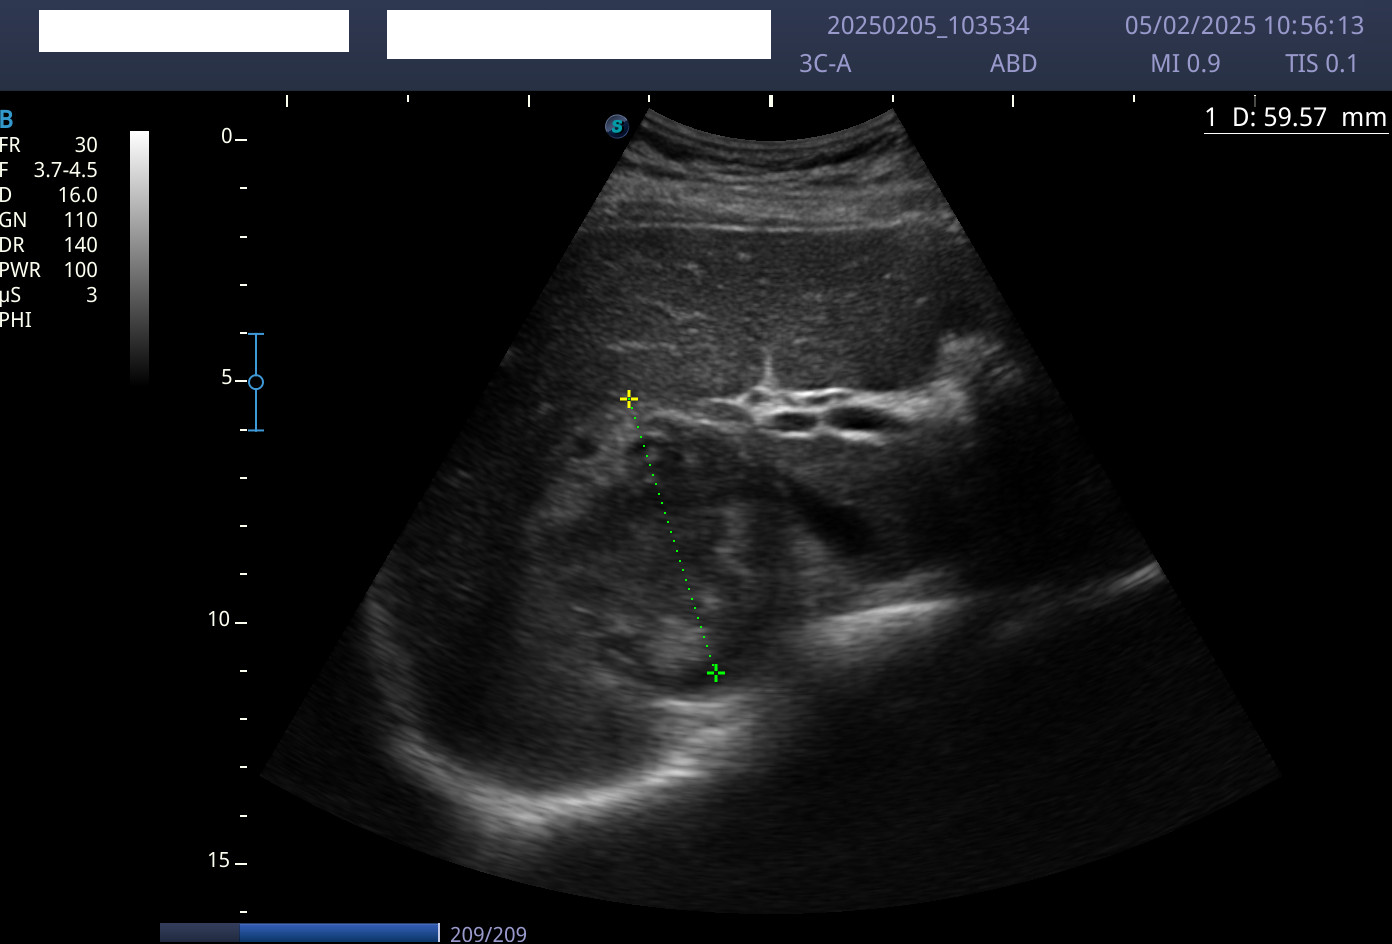

Como venía en seguimiento por dolor lumbar derecho, se procedió a realizar una ecografía de abdomen. Se encontró una masa sólida heteroecogénica, con alguna calcificación, bien delimitada, a nivel suprarrenal derecho de unos 60 x 80 mm.

Juicio clínico: tumor en la glándula suprarrenal derecha con metástasis cutáneas.

Diagnóstico diferencial: neoplasia adrenal maligna primaria (carcinoma adrenal o feocromocitoma) versus metástasis de carcinoma de pulmón, mama, melanoma, digestivo o renal. En cuanto a las lesiones cutáneas, el diagnóstico diferencial incluiría procesos infecciosos, traumáticos (hematoma organizado) o lesiones neoplásicas malignas (sarcoma, linfoma o metástasis cutáneas).